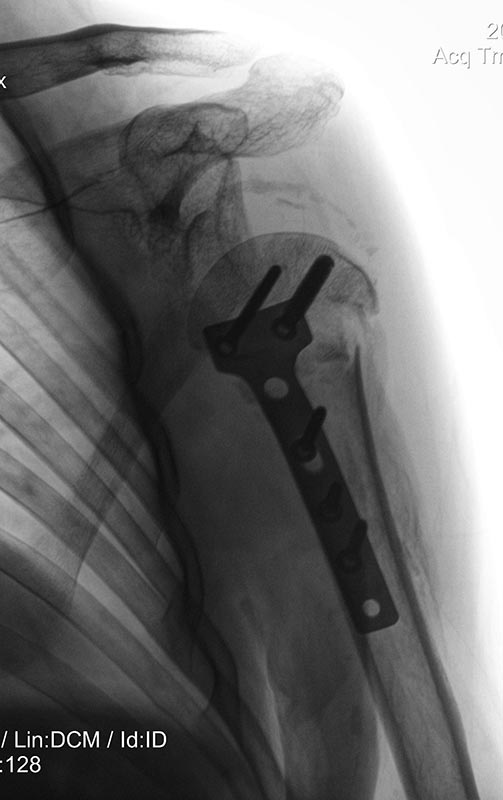

Синтезированный перелом плеча, невправленный вывих |

Закрытый оскольчатый переломо-вывих шейки, головки левого плеча с импакцией и дефектом костной ткани, отрыв ротаторной манжеты. Больной, мужчина 44-х лет.Поступил в отделение травматологии после бытовой травмы. При поступлении проведена блокада места перелома, закрытая ручная репозиция, наложена мягкая повязка Дезо. Не спрашивайте почему (праздники, перераспределение больных), но - через 2 недели проведена операция: открытое вправление вывиха левого плеча, остеосинтез пластиной, трансартикулярная фиксация спицами. Ведение в повязке Дезо.

Послеоперационный период без особенностей , послеоперационная рана зажила первично. Черезмесяц спицы удалены. Через два месяца обратился с признаками переднего вывиха левого плеча. Отведение плеча отсутствует. Извините, но первоначальных снимков нет.

Планируется вправление плеча, рефиксация ротаторной манжеты, трансартикулярная фиксация спицами. С последующим ведением на отводящей шине.

Уважаемые коллеги посоветуйте, пожалуйста, по дальнейшей тактике лечения данного пациента, какое лечение предложили бы вы?